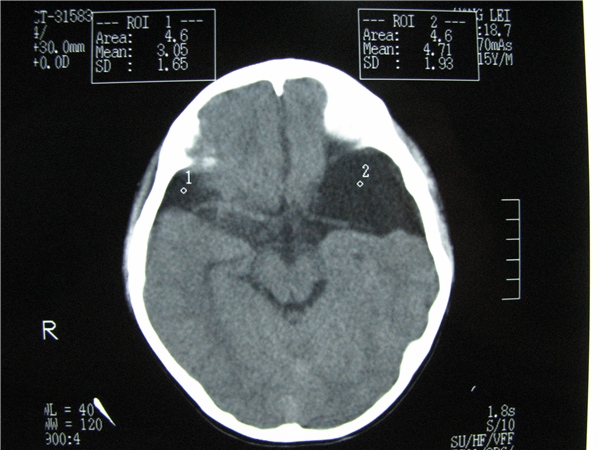

标题: CT20748:M 15Y 头痛,以前有外伤史请老师看看除了囊肿还有别 [打印本页]

标题: CT20748:M 15Y 头痛,以前有外伤史请老师看看除了囊肿还有别

m 15y 头痛,以前有外伤史请老师看看除了囊肿还有别的吗?

蛛网膜囊肿。眼拙,看不出别的,倒是看到了双侧大脑中动脉影,类似“致密动脉征”。

双侧侧裂池和纵裂池近前颅窝蛛网膜囊肿。

不能除外脑穿通畸形

无明显占位及负占位效应,考虑软化灶并脑室穿通畸形囊肿、局限性脑萎缩

蛛网膜囊肿,不能除外脑穿通畸形,支持。